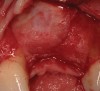

Figure 2  (Case 1) Condition of implant at surgical exposure.

Figure 2

Figure 3  (Case 1) Removal of implant was accomplished using piezo-surgery in order to maintain the lingual plate. Note that trephines are not recommended for this procedure.

Figure 3